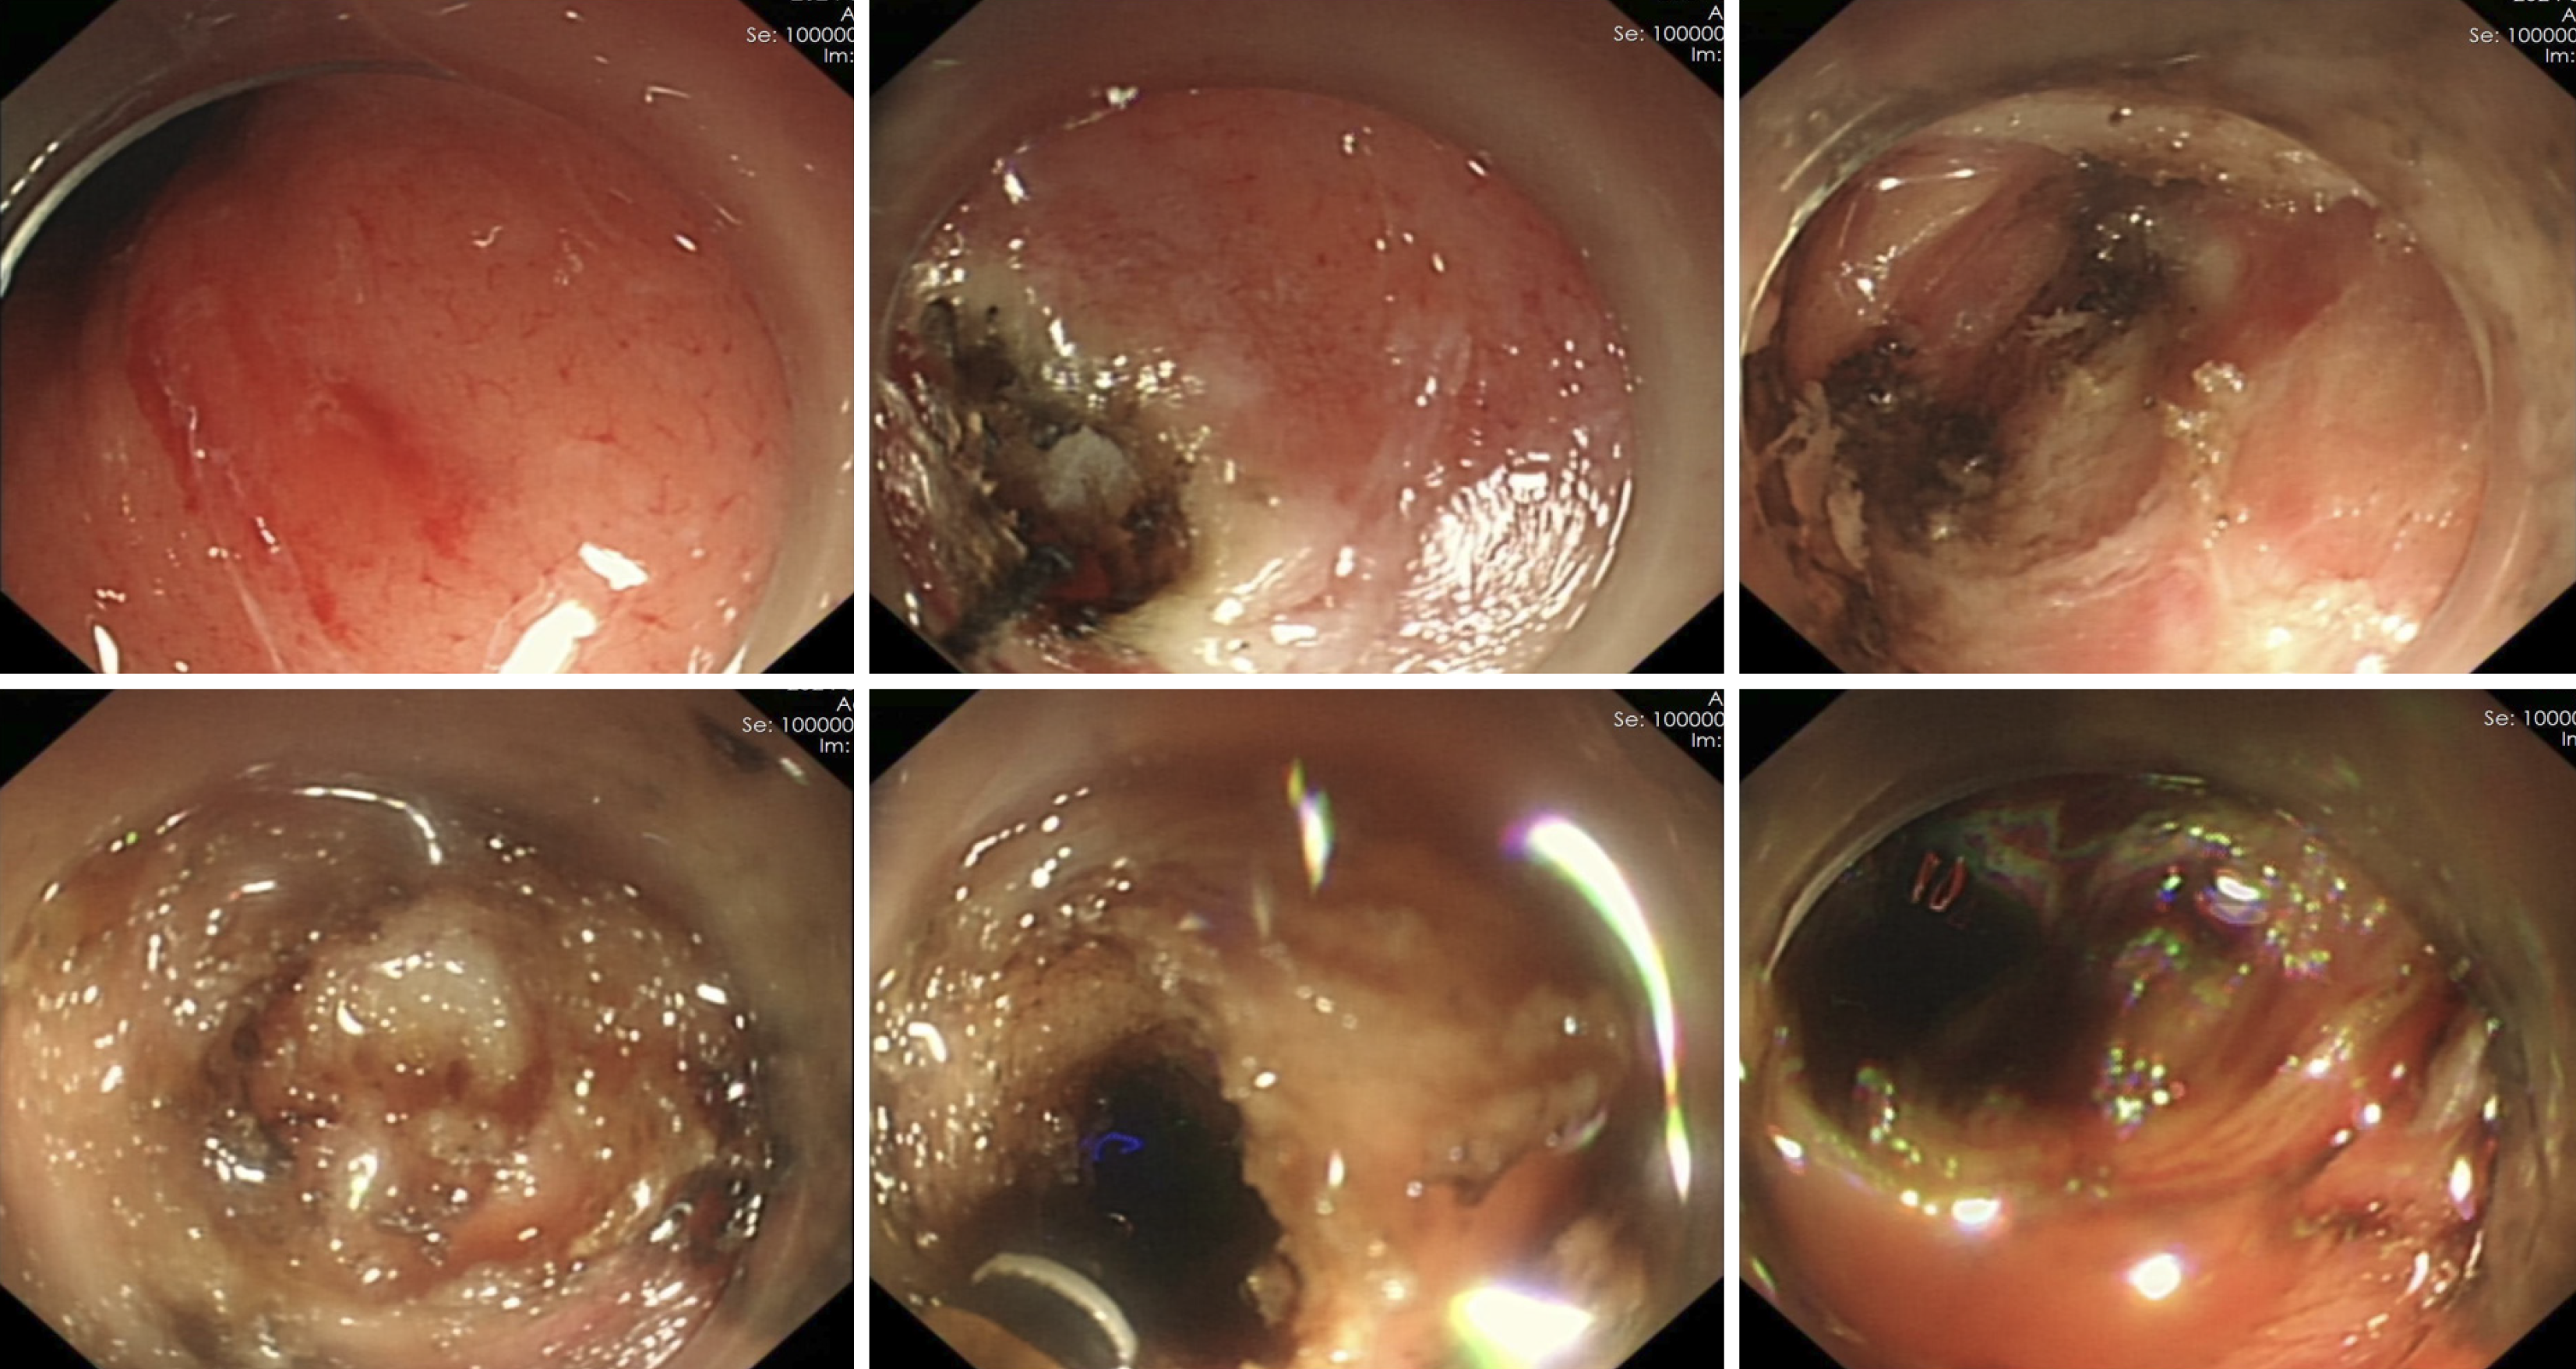

Under general anesthesia with endotracheal intubation, endoscopic ultrasound revealed a circular hypoechoic lesion in the body of the pancreas, with scattered areas of increased echogenicity (Figure 2). A 23G needle was utilized for puncture, yielding a coffee-like fluid. The puncture site was marked, and a Dual knife was employed to incise the gastric wall, exposing white, wall-like tissue. Upon aspiration with the puncture needle, a significant amount of coffee-like fluid was observed, prompting a deeper incision at the site, resulting in a substantial outflow of fluid (Figure 3). The endoscope was subsequently inserted into the cystic cavity to facilitate further aspiration, revealing a flocculent substance at the base. Hemostasis was achieved, and a gastric tube was placed (Figure 4).